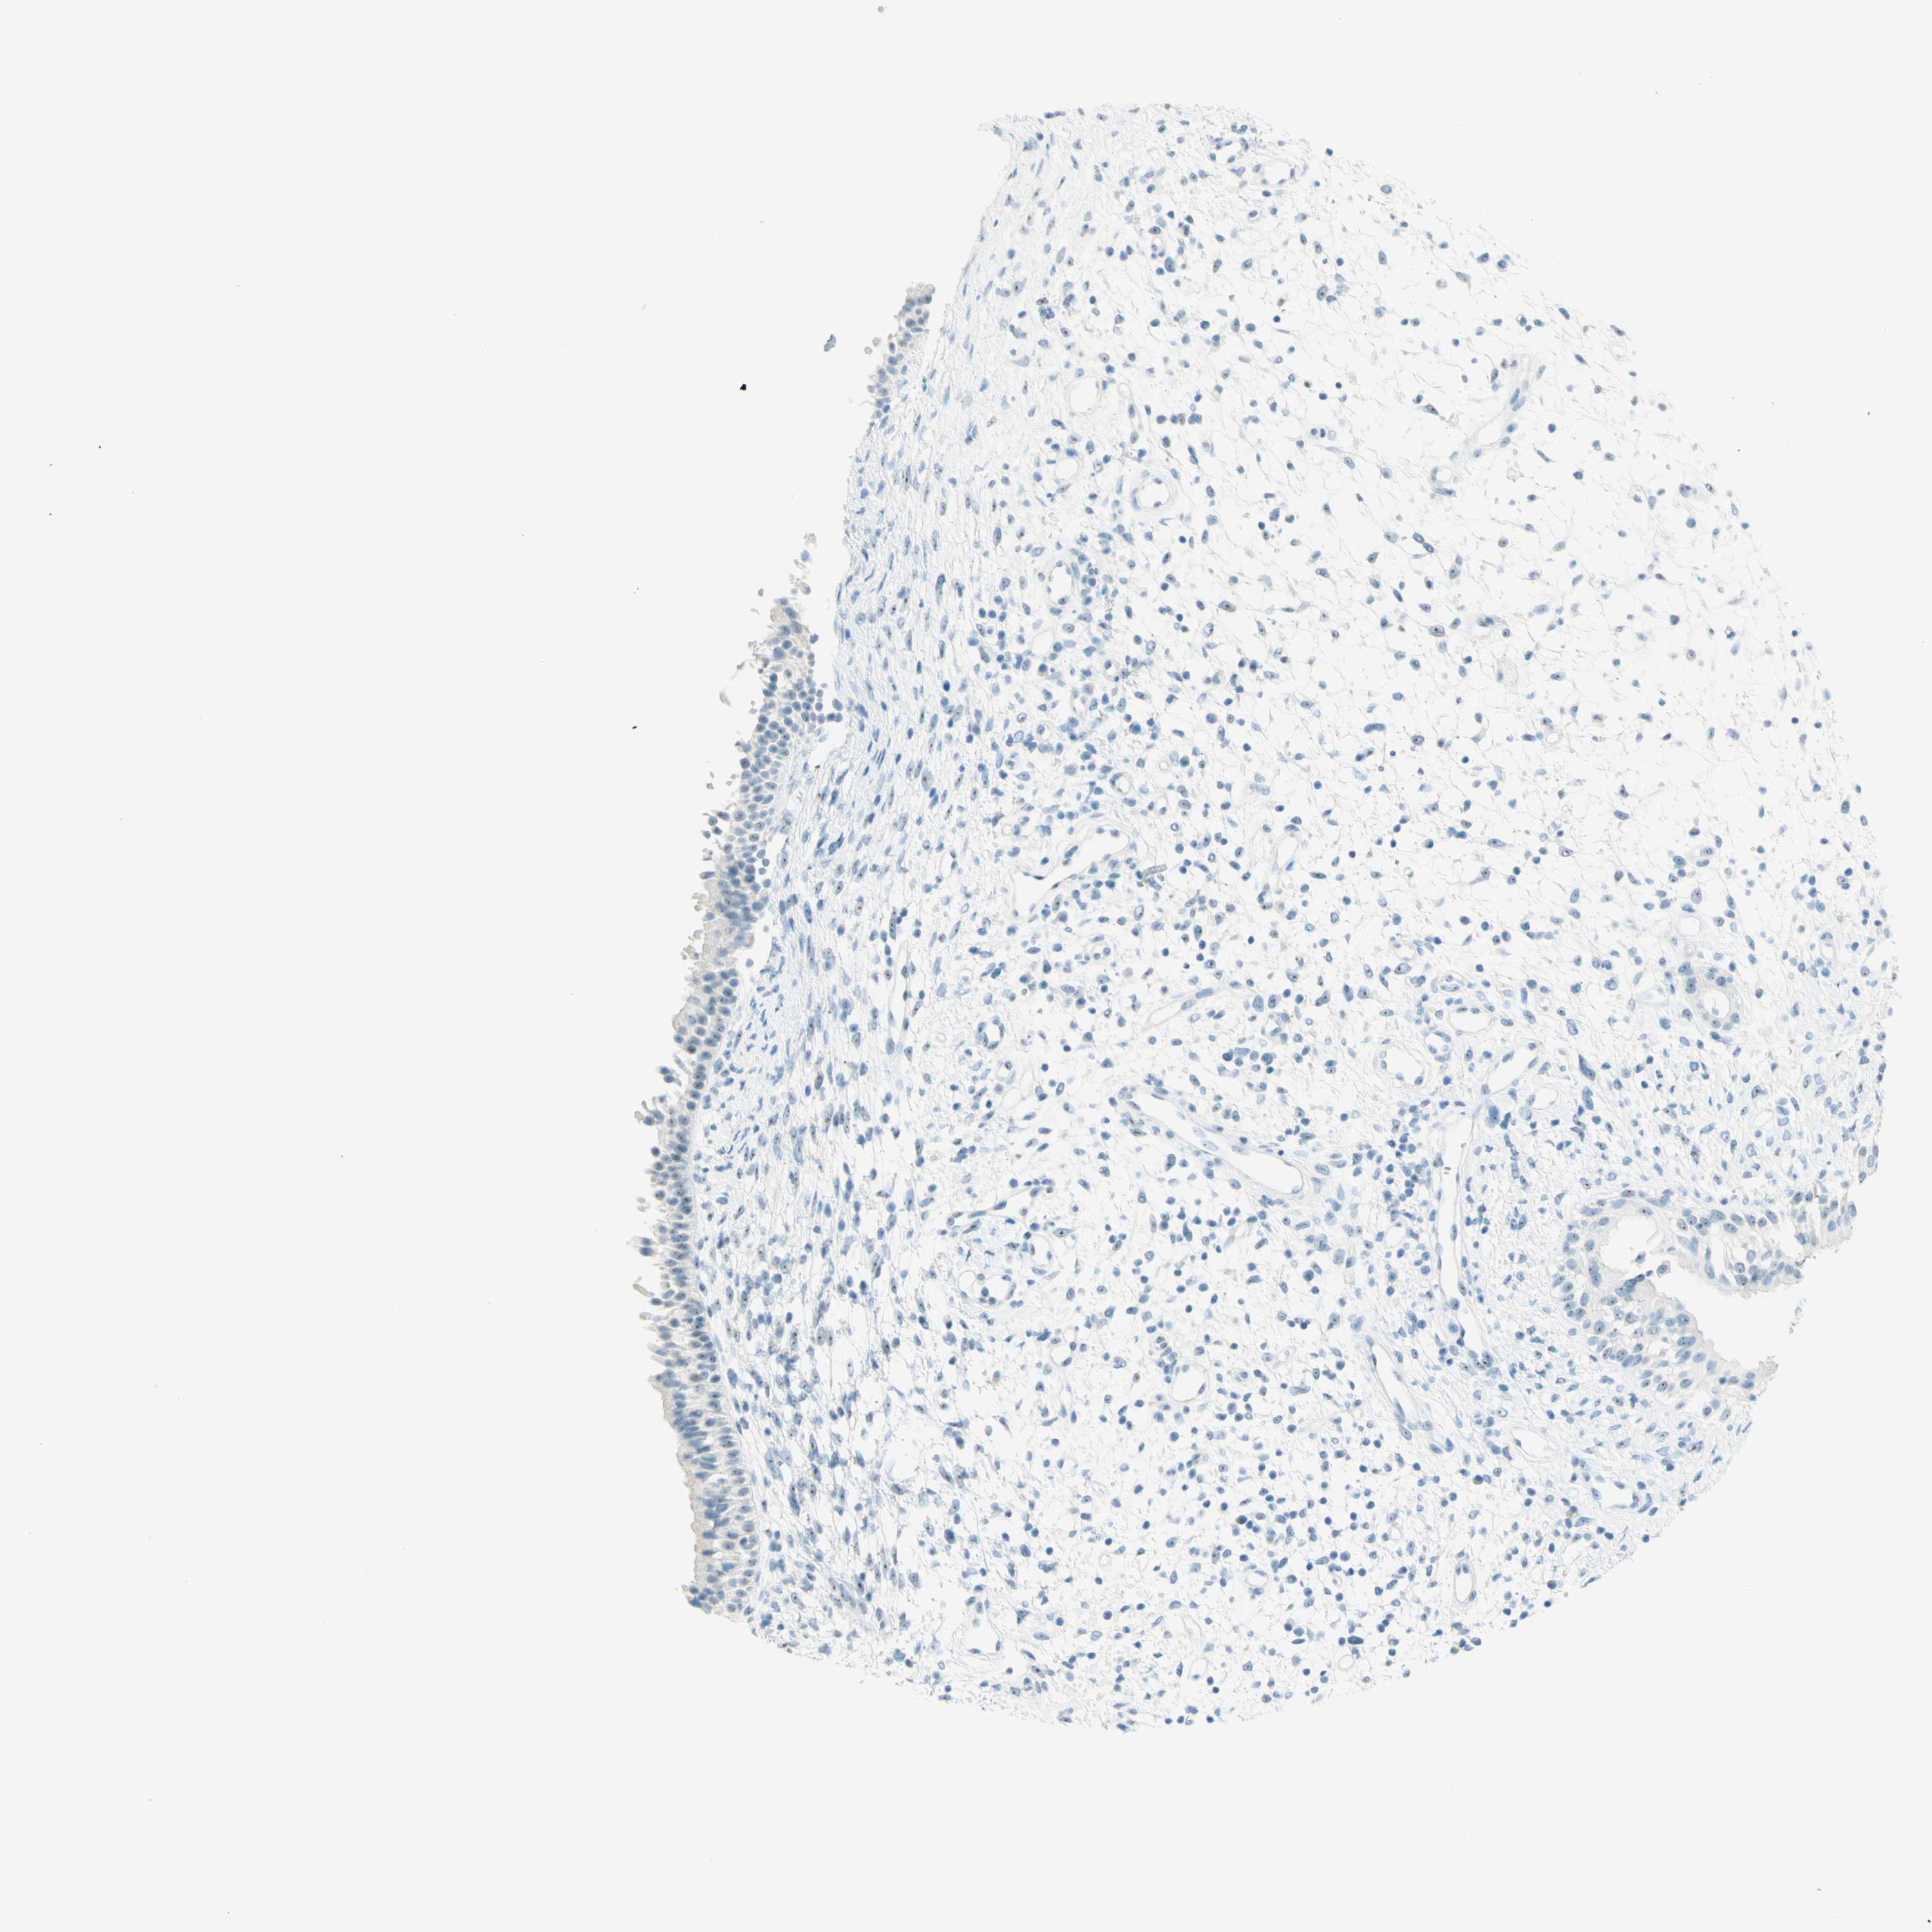

NASOPHARYNX - Antibody stainingi

Antibody staining in the annotated cell types in the current human tissue is reported as not detected, low, medium, or high, based on conventional immunohistochemistry profiling in selected tissues. This score is based on the combination of the staining intensity and fraction of stained cells.

Each image is clickable and will lead to virtual microscopy that enables deeper exploration of all samples and also displays staining intensity scores, fraction scores and subcellular localization as well as patient and tissue information for each sample.

Antibody HPA011284Antibody CAB026403

Respiratory epithelial cells LowNot detected